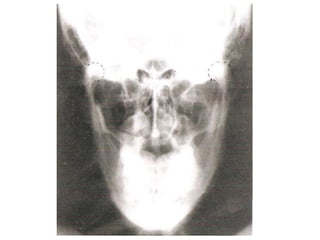

Radiografia do crânio

• Estruturas internas são mais estudadas com aquisições de

imagens mais detalhadas.

Alterações visualizadas:

Fraturas;

Neoplasias;

Inflamações;

Distúrbios articulares (ATM);

Lesões por PAF;

Adenomas hipofisários;

Mieloma múltiplo;

Doença de Paget (osteíte deformante).

Processo odontoide